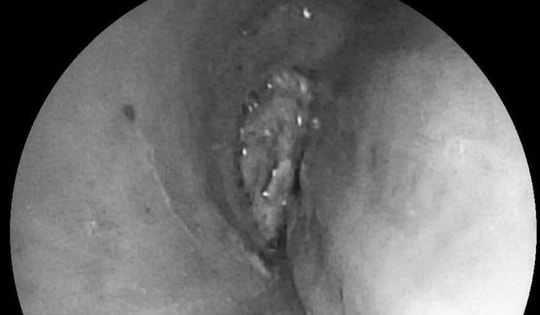

Người phụ nữ 57 tuổi bị tức ngực, bác sĩ gắp ra thứ "đáng sợ" bên trong